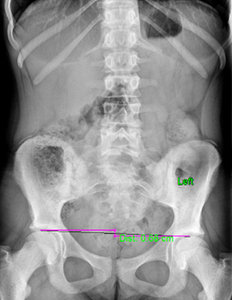

FIG 2 X-ray showing 6.8 mm femoral head height difference, higher on the right.

I then looked at her X-rays. The most important view is the A-P L-S. We took the first series barefoot. On this view, I first looked at femoral head height. She had a 6.8 mm femoral head height difference, higher on the right. (Fig. 2) On her lateral L-S view, she had a lumbarization, removing the ability to know exactly what her Ferguson's center of gravity showed, as well as her sacral base angle. On lateral cervical (Fig. 3), she had a straight cervical spine, often associated with chronic headaches. The open-mouth view (Fig. 4) showed the significant imbalance between atlas and axis.

Based on the digital laser foot scan, I ordered full-length stabilizing orthotics with three-arch support. Once the orthotics arrived, I put them in the patient's shoes and re-took the A-P L-S view to see how the orthotics affected femoral head height. The repeat X-ray of the A-P L-S showed there is now a 5.0 mm femoral head height difference, (Fig. 5), showing orthotics help reduce the difference. However, a heel lift was still needed. I applied a 5 mm heel lift to the left orthotic.

FIG 5 A-P L-S view indicating a 5.0 mm femoral head height difference following use of orthotics.